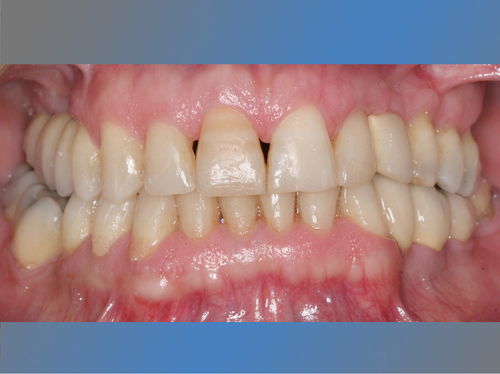

Félix Miquel Sempere acude en 2001 a la clínica dental IDIM tras varios intentos fallidos de colocación de implantes dentales en otra clínica dental.

También se le sustituya el puente de la mandíbula que presentaba movilidad debido a caries en los dientes pilares por dos implantes y se le coloca otro implante en un canino superior ausente.

Después de 17 años los implantes siguen estables y sanos. Félix tiene una sonrisa completa y una boca sana, y nos cuenta que va tan bien que no distingue entre sus dientes naturales y los implantes.